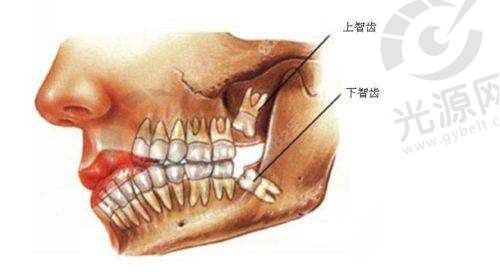

智齿拔牙是许多人在成长过程中的一道难关,而了解智齿拔牙后窟窿修复图,可以帮助您更好地应对这一过程。智齿的生长常常伴随着疼痛和不适,尤其是当它们位置不正或受阻生长时,拔除智齿成为了必要的选择。 在拔牙后的修复过程中,患者往往会关心拔牙后的伤口愈合情况,以及正常修复的标准。本文将详细介绍拔智齿后的伤口愈合情况,通过智齿拔牙后窟窿修复图,帮助您了解拔牙后7天、14天、30天的伤口状态和修复进程。并且,我们还将结合医学数据和实际实例,为您提供关于拔智齿后修复的科学认识和行动指南。通过对这些信息的深入理解,您将能更有信心地渡过拔牙后的修复阶段。

在智齿拔牙后,伤口的愈合是每位患者更为关心的事情之一。智齿拔牙后窟窿修复图能够直观展示拔牙后伤口在不同时间阶段的愈合过程,帮助患者更清晰地了解自己的修复情况。研究显示,在拔牙的后的第一个星期,伤口的自我愈合已开始慢慢展现,通常在这一阶段患者会感到疼痛和肿胀,而这也是完全正常的。

通过观察智齿拔牙后窟窿修复图,患者可以了解到,伤口周围组织的再生与愈合过程是一个逐步的过程。在拔牙后的7天内,伤口周围的组织会开始形成一种叫做肉芽组织的物质,这是愈合过程中非常重要的一步。